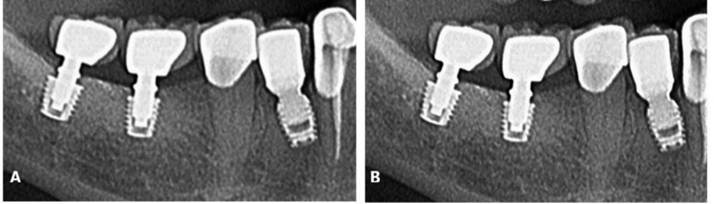

Paciente A. R. S, gênero feminino, 67 anos de idade, compareceu ao consultório particular, em 2020, com a queixa de mobilidade na região dos implantes inferiores. Na anamnese, paciente realizava acompanhamento médico devido ao quadro de diabetes mellitus, com uso de medicamentos específicos. Ao exame clínico, verificado mobilidade acentuada na regão do 36, 37, 46 e 47. Foram solicitados radiografia panorâmica (Figura 04. A) e tomografia computadorizada da área, evidenciando comprometimento periodontal avançado nas reabilitações com implantes dentários. O plano de tratamento proposto foi a remoção dos implantes e nova reabilitação da região atrófica.

Inicialmente, o procedimento cirúrgico consistiu pela remoção dos implantes dentários (Figura 04. B), realização de enxerto imediato (Bio-Oss, Geistlinch, Wolhusen – Suíça), através da técnica de reconstrução tipo tenda, e uso da membrana de colágeno (Bio-Gide, Geistlinch, Wolhusen – Suíça). O Quadro 1 apresenta as principais medidas para avaliação do posicionamento do implante. Após 6 meses, foram instalados dois implantes dentários extra curtos ARCSYS (FGM, Joinvile – SC, Brasil) 4,0 mm x 6,0 mm x 5,0 mm do lado direito e dois implantes na região esquerda 5,0 mm x 5,0 mm. As figuras 05 e 06 evidenciam aspecto radiográfico após a etapa inicial. As recomendações pós-operatórias e a prescrição medicamentosa foram realizadas, resultando em ausência de complicações após a intervenção. O acompanhamento foi feito durante 5 anos, com resultado satisfatório (Figura 7. A – E).

| Dente 35 | Dente 36 | Dente 37 | Dente 46 | Dente 47 | |

| Medida do implante ao canal mandibular | 1,73mm | 1,39mm | 0,72mm | 1,50mm | 2,00mm |

| Medida da parede vestibular a lingual | 9,37mm | 9,88mm | 9,43mm | 8,47mm | 9,90mm |

| Medida do implante a parede vestibular | 2,72mm | 3,33mm | 2,27mm | 2,28mm | 3,42mm |

| Medida da plataforma do implante a crista óssea | 1,56mm | 0,83mm | 1,22mm | 1,34mm | 1,84mm |

| Medida da anilha a plataforma do implante | 11,00mm (compensar 2mm) | 11,00 mm (compensar 2mm) | 11,00mm (compensar 2mm) | 11,00mm (compensar 2mm) | 11,00mm (compens ar 2mm) |

| Medida da anilha ao ápice do implante + 2mm da chave redutora | 18,00mm | 18,00mm | 19,00mm | 19,00mm | 19,00mm |

Fonte: Autoria propria

Figura 05. Exames de imagem da região inferior direita. A) Vista panorâmica. B) Reconstruções tridimensionais. C) Cortes transversais oblíquos.

Figura 06. Exames de imagem da região inferior esquerda. A) Vista panorâmica. B) Reconstruções tridimensionais. C) Cortes transversais oblíquos.